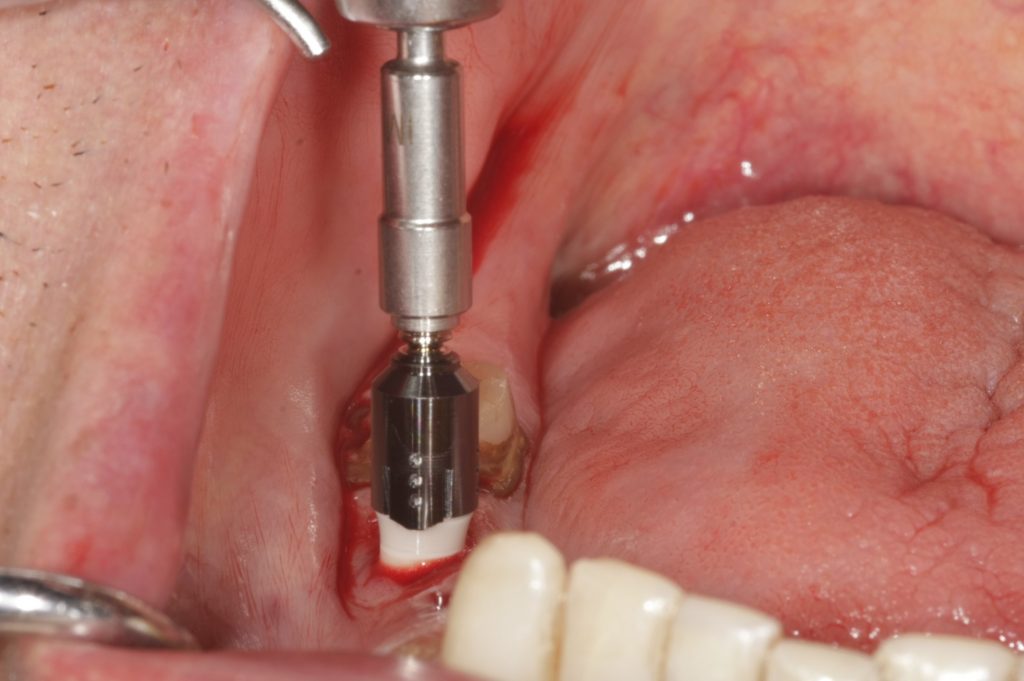

Autores: PRÓLOGO Asimismo, desde el punto de vista pedagógico, el profesional nobel en la materia tiene a su alcance la posibilidad de corregir cualquier posición implantaría en el ordenador, planear los provisionales y plasmarlos en la bio réplica antes de tocar al paciente a operar. Todos estos razonamientos nos llevan a presentar un caso de condiciones muy favorables para poner en práctica estos métodos como primer acercamiento a una Odontología Digital de alta calidad, con medios informáticos, que ya están presentes en la profesión de hoy en día, y será la protagonista única del futuro. Por otro lado, después de numerosos estudios que nos llevan a plantear el “gap” entre implante y pilar(abuttment), como principal responsable de la periimplantitis dado que la microbiota presente en el mismo es imposible de limpiar y en su presencia la cortical ósea reacciona reabsorbiéndose, nos ha llevado a utilizar implantes monobloc ya que los ejes implantarios y protéticos coincidían, y nos permitían su uso. Además, el circonio, ha mostrado a la luz de estudios muy recientes, una preservación y adhesión de los tejidos blandos superiores al titanio, tanto en su tratamiento de superficie de la rosca como a nivel gingival. DESARROLLO Paciente varón de 68 años, con antecedentes de radio/quimioterapia cinco años antes, con Rehabilitación Oral de los cuatro cuadrantes, con una Oclusión Mutuamente Compartida conservada, (REF.8) la que fracasa en el cuadrante 4, 19 años después. El mismo presentaba un puente de porcelana sobre circonio con pilares en 44 y 47, reemplazando el edentulismo de 45 y 46. Se produce la fractura del PM del 44, y ante una endodoncia antigua y corta, se decide implantar las zonas edéntulas, conservando temporariamente los pilares, hasta producida la oseointegración, para entonces también exodonciar el 44. DIAGNÓSTICO Tomamos impresiones del maxilar antagonista, Arco Facial Estático y realizamos montaje del mismo mediante la sistemática ARTEX. Producimos la relajación del músculo Pterigoideo Externo, para obtener la ORC (Oclusión en Relación Céntrica) mediante el método de Laminillas de Long, basado en el concepto de INERVACIÓN RECÍPROCA. Esto nos permitirá montar el maxilar inferior, tanto en su forma de: La primera para practicar la cirugía guiada y comprobar su eficacia, y el modelo de yeso para ser escaneado y confeccionar la GUÍA QUIRÚRGICA. La Biorréplica la obtenemos transformando los archivos DICOM que nos da el CBCT en archivos STL, y a partir de ellos, mediante una tecnología de PROTOTIPADO RÁPIDO, la obtención de un objeto físico en 3D a través de la aglutinación selectiva de una sucesión de capas de polvo. Procedemos a montar la biorrèplica y el modelo de yeso del caso. Podemos verificar la exactitud de las medidas del hueso residual en la bio réplica y compararlas con el scanner. Arrojando un resultado de 8,5 mm de cortical externa a cortical externa. Pudiendo también medir la distancia hasta el dentario. y comparar gracias a la ventana lateral de la biorréplica Dándonos 22mm de distancia. Con lo cual deducimos que implantes de 4,1mm por 12 mm serán perfectamente rodeados de hueso. Medimos también la distancia desde oclusal del antagonista, hasta el hueso desnudo. Lo mismo que, mediante la utilización de la guía radiológica, con un material radiolúcido colocado en gingival de la misma, podemos medir la altura de la encía. Con lo cual podemos calcular la altura del pilar. Es entonces cuando con el programa COC Diagnostix se realiza la programación final: Obteniendo no solo la ubicación, largo, ancho y ángulo de los implantes sino también los provisionales mediante CAD CAM. Ya entonces podemos hacer la práctica quirúrgica en la bio réplica, mediante la guía quirúrgica, instalando los implantes de prueba que no serán los de circonio, ya que la casa no cuenta con ellos, pero si otros de las mismas dimensiones. TRATAMIENTO Entramos ya en la cirugía propiamente dicha. Antisepsia de la zona a operar y zonas anexas. Comprobación del perfecto ajuste e inmovilidad de la G.Q. en boca durante la cirugía. Marcado de la encía y perforación de la cortical. Visión a través de la Guía de la mínima intervención anterior. Comprobación sin Guía. Incisión mínima mesio distal, para apartar y conservar encía queratinizada. Secuencia de drills, perforando a profundidad requerida Observación del Mínimo Trauma Implantes Strauman de Zirconio Monoblock en blíster y montádo en contrángulo reductor. Instalación controlando torque con contrángulo reductor. Comprobación clínica. Comprobación Radiográfica y con Guía. Toma de impresiones, y armado de modelos con técnicas de pasividad protética. Montaje. Resultado de las provisionales ejecutadas por CAD CAM Al no estar conformes con el resultado decidimos desechar dichas provisorias y optar por repetirlas. Nuevas provisorias realizadas mediante encerado convencional. Estado de los tejidos blandos. Provisorias en boca. Oclusión de Estímulo Inmediato. Ref.10: Carga inmediata .Alberto y Diego Bechelli. Comprobación mediante CBCT post operatorio Componentes del equipo (En la próxima presentación, mostraremos las coronas definitivas de porcelana sobre circonio, y la desoclusión provocada por una OCLUSIÓN MUTUAMENTE COMPARTIDA, sobre estos implantes y otros seis mas) REFERENCIAS

Instalación de Talla de Campo Operatorio.

Instalación de Separador Labial Quirúrgico.

Comprobación intraoperatoria de la Guía Quirúrgica.

FIG:47-48-49

FIG:50-51-52-53-54

Fig. 50

Fig. 51

Fig. 52

Fig. 53

Fig. 54

FIG:55

FIG:56

FIG:57

FIG:58